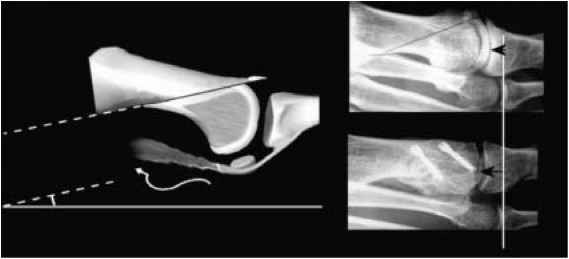

Decompressive metatarsal osteotomy

This involves shortening the metatarsal bone. The bone is cut at an angle and slid back or a small section of bone is removed. In either case fixation is used to maintain the new position whilst the bone heals. This procedure is selected when the 1st metatarsal is longer than the 2nd and when there appears to be adequate cartilage on the joint surfaces to allow movement.